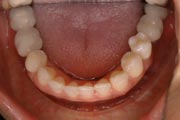

Crowding

After